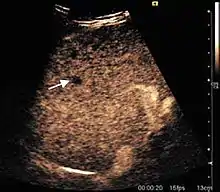

Encephaloid hepatocellular carcinoma (CEUS). Contrast tumor enhancement is observed on the left during arterial phase. The “wash-out” phenomenon can be seen on the right, during portal venous phase.

HCC appearance on 2D ultrasound is that of a solid tumor, with imprecise delineation, with heterogeneous structure, uni- or multilocular (encephaloid form). An "infiltrative" type is also described which is difficult to discriminate from liver nodular reconstruction in cirrhosis. Typically HCC invades liver vessels, primarily the portal veins but also the hepatic veins . Doppler examination detects a high speed arterial flow and low impedance index (correlated with described changes in tumor angiogenesis). The spatial distribution of the vessels is irregular, disordered. CEUS examination shows hyperenhancement of the lesion during the arterial phase. During the portal venous phase there is a specific "wash out" of ultrasound contrast agent (UCA) and the tumor appears hypoechoic during the late phase. Poorly differentiated tumors may have a stronger wash out leading to an isoechoic appearance to the liver parenchyma during portal venous phase. This appearance was found in approx. 30% of cases. The described changes have diagnostic value in liver nodules larger than 2 cm.